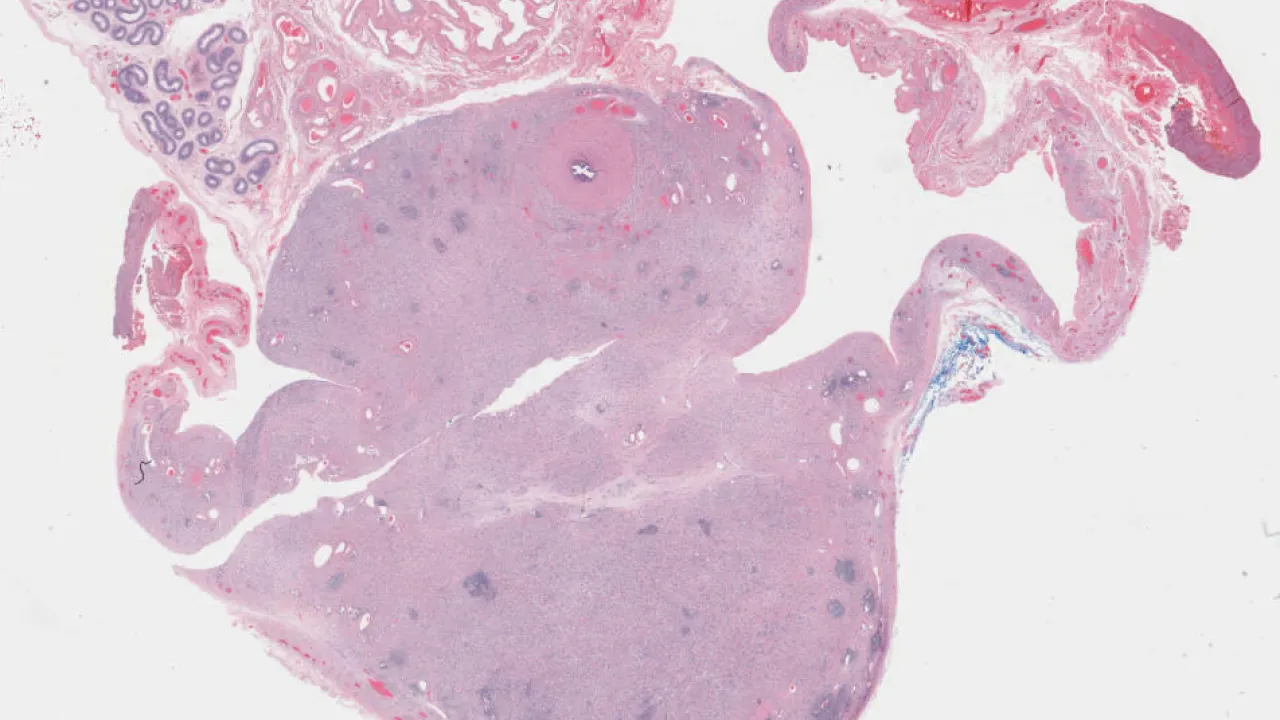

Lymph Nodes, Follicular lymphoma, H&E stain